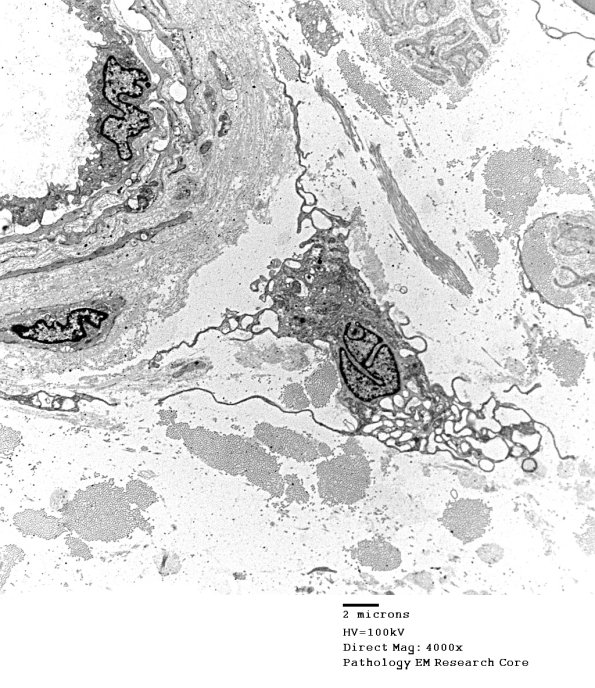

1C4A-C Successively higher magnification images of a vacuolated fibroblast. (electron micrographs)